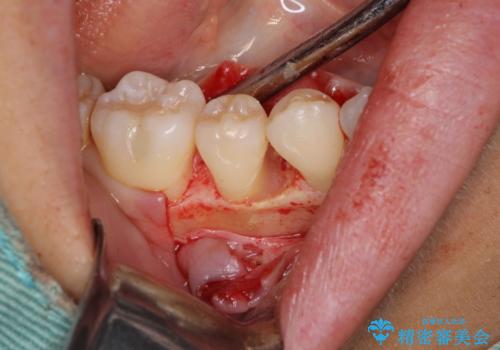

患者様は、他院で右下の歯を抜歯かもと言われました。全体の歯周病はなく、右下の1歯だけ骨が極端に減少していました(初診時歯周ポケット7mm。通常は3mm以下。)。その歯だけ咬合が強いことが原因と考えられたため、咬合を弱くする処置と減少した骨を再生する処置が必要になりました。

骨の再生治療手術をして10か月経過観察をしたのち、骨を平坦化する手術を行い、治療終了となりました。